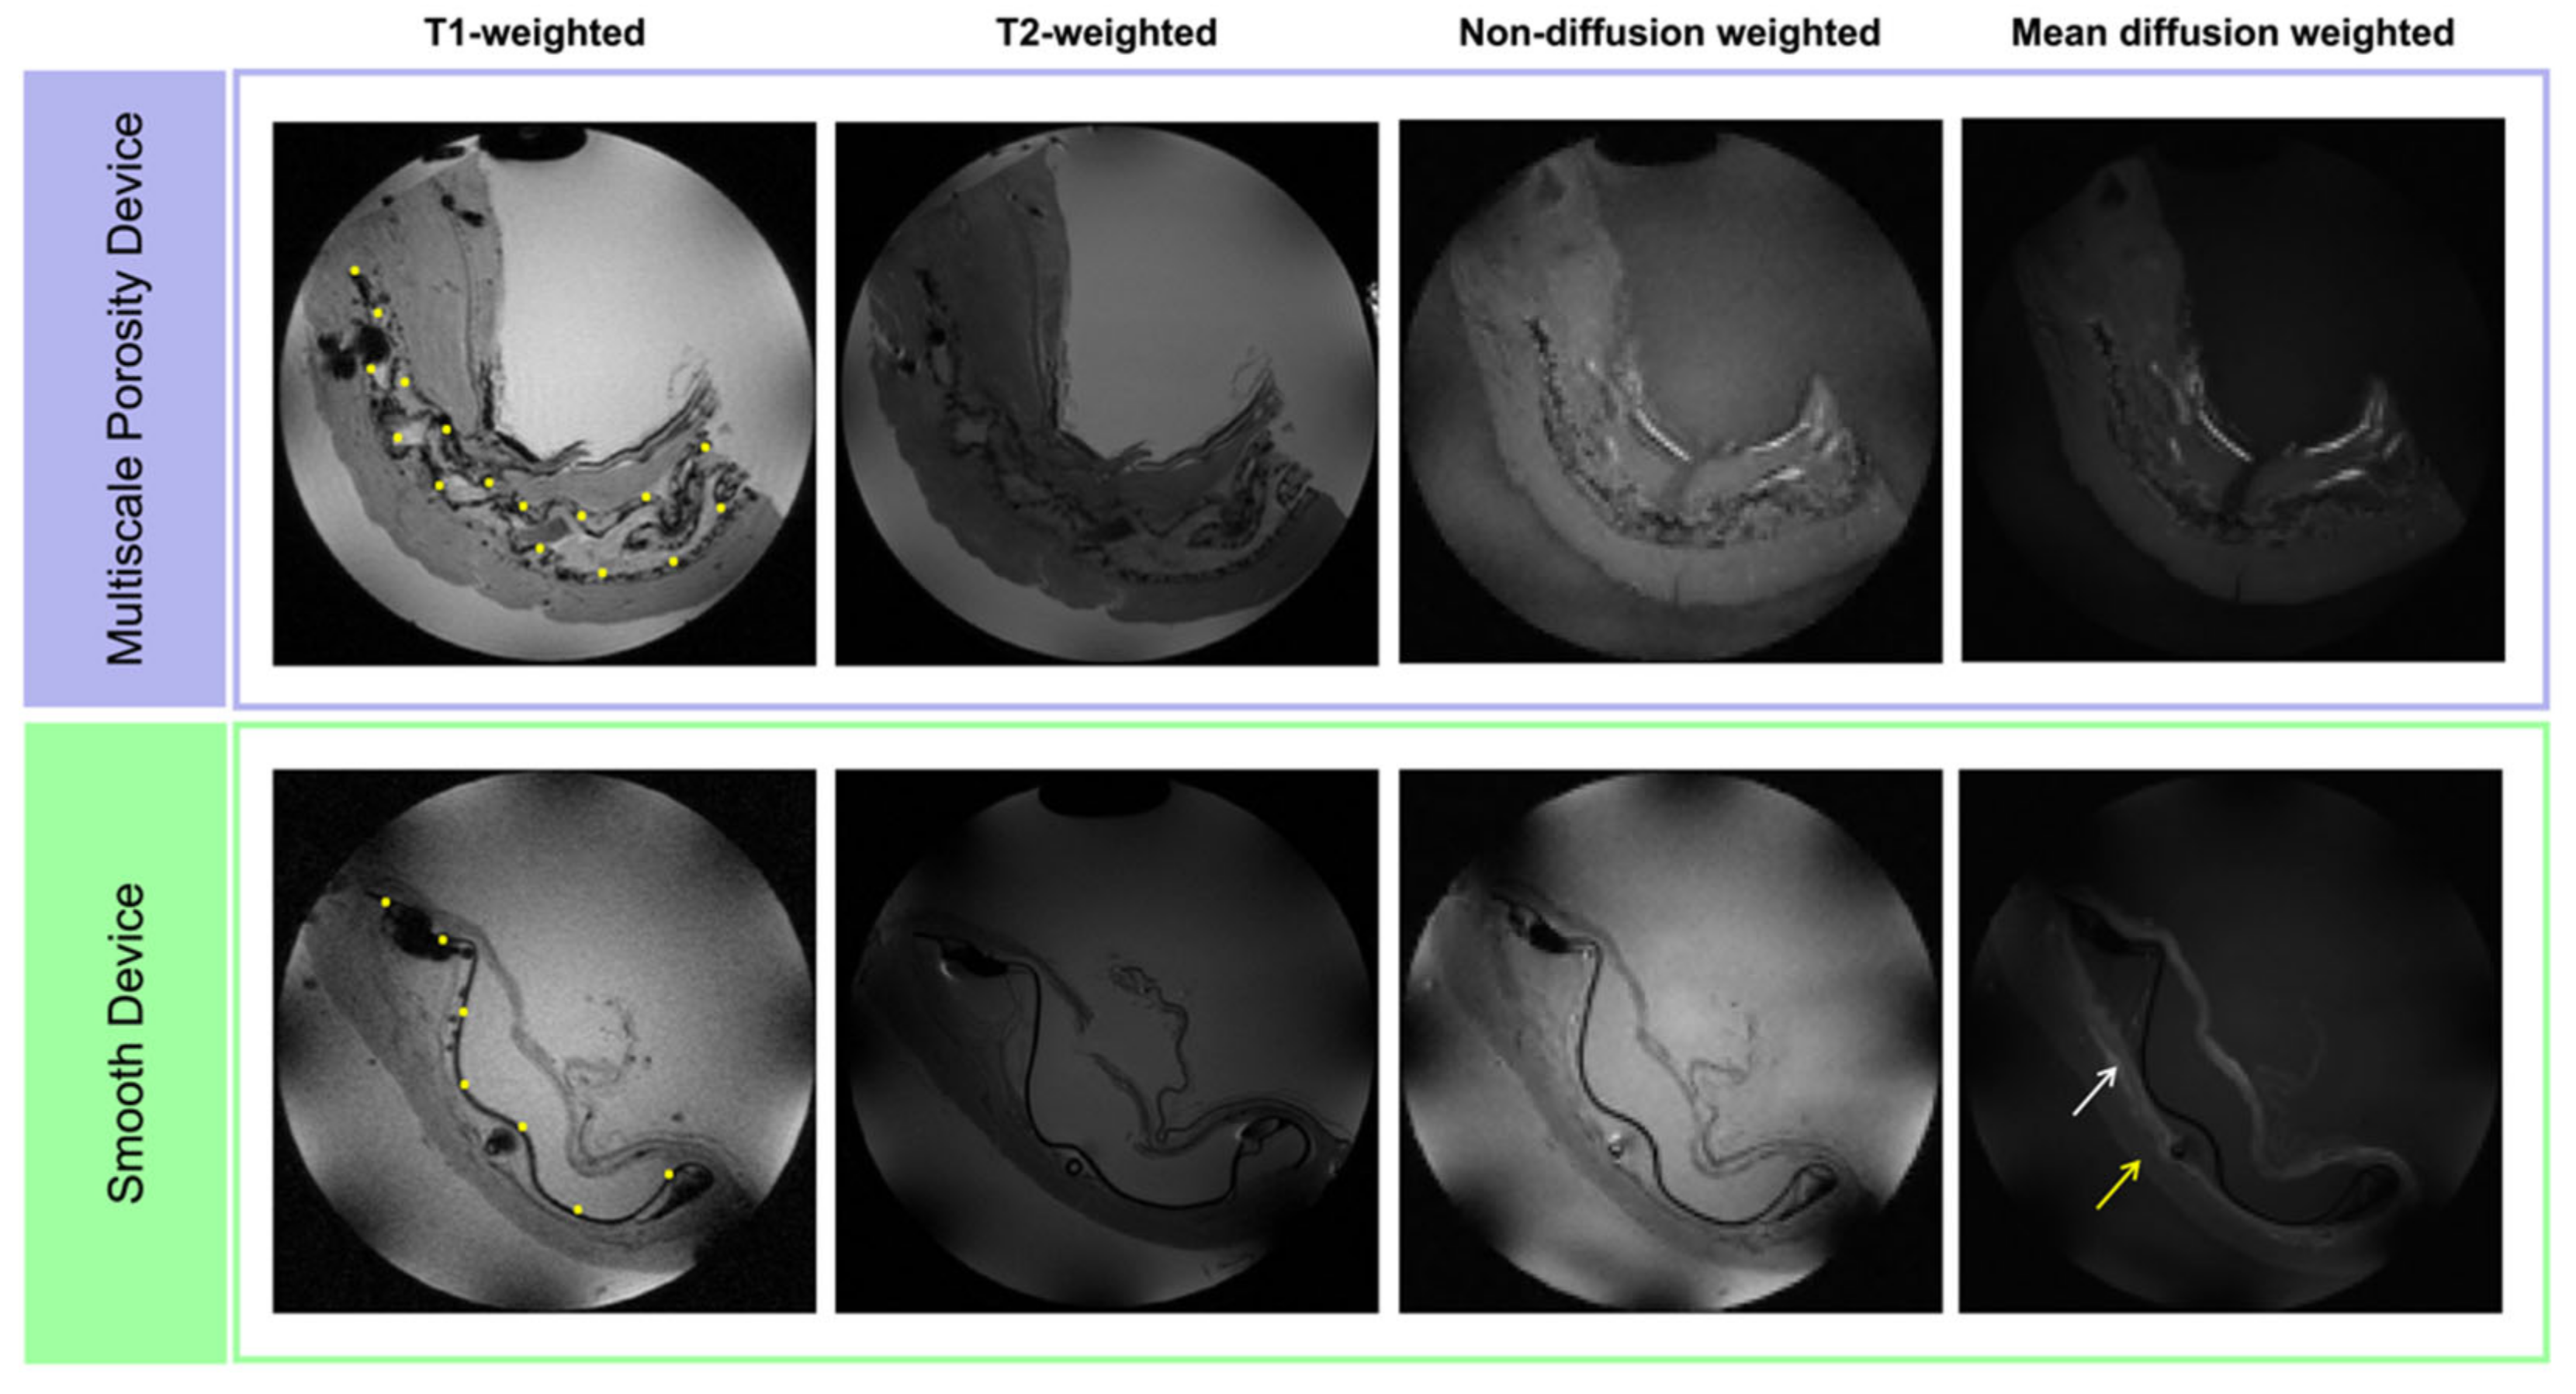

3.2. Multi-Contrast MRI